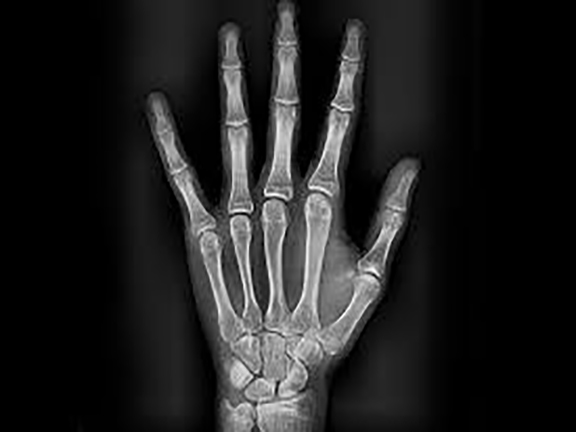

Ofrecemos la más alta tecnología con una atención profesional y personalizada por parte del equipo altamente calificado en donde contará con el mejor estudio para sus pacientes.